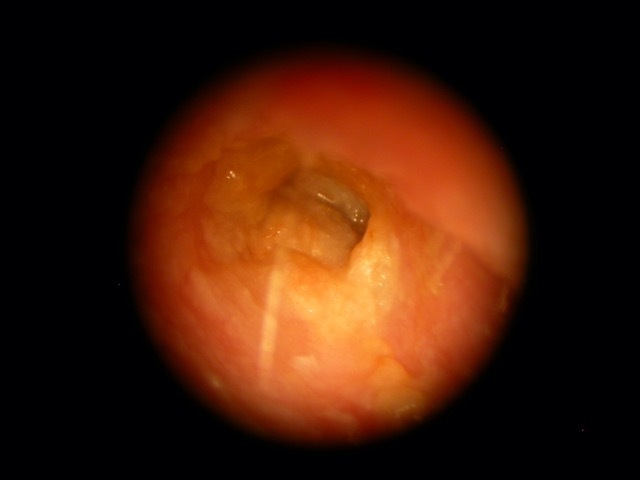

CSOM

Perforation

Tympanic Membrane